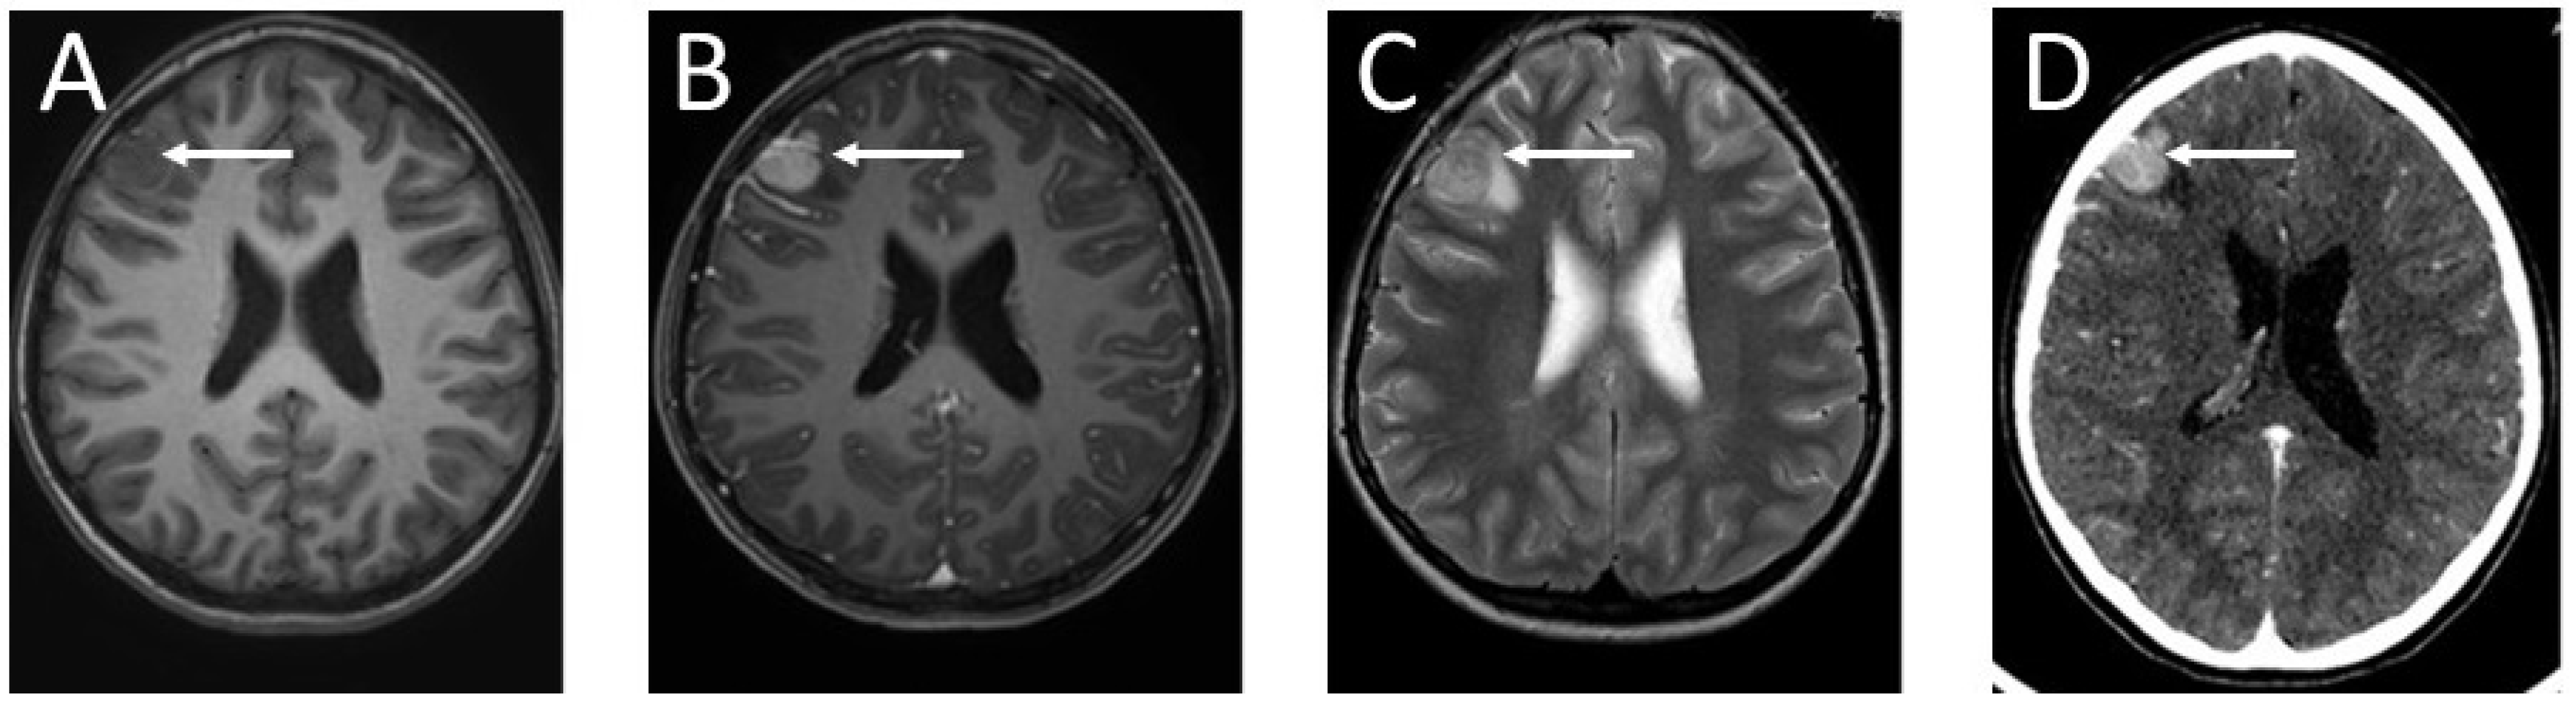

The girl was discharged from hospital. She was under the care of the outpatient clinic. Eight months later, the patient was admitted to hospital due to an epileptic seizure. The child’s mother claimed that the girl had complained of double vision a month earlier. Neurological examination revealed paresis of the right sixth cranial nerve. The child complained of diplopia when looking straight ahead and to the right. A fundoscopy revealed bilateral optic disc edema. The girl underwent a two-phase contrast-enhanced computed tomography (CT) followed by an MRI (Figure 5). In the right frontal area, a well-enhanced, spherical tumor, measuring 16 × 17 × 17 mm, was visible. It was surrounded by a 7 mm peritumoral edema zone. The ventricular system of the brain was slightly enlarged, but without signs of active hydrocephalus.

Figure 5.

Imaging of the brain tumor: (A) T1-weighted MRI of the patient’s head without contrast enhancement—the brain tumor is visible as a hypointense lesion in contrast to the white matter, located in the right frontal lobe; (B) contrast-enhanced T1-weighted MRI—the mass in the right frontal region shows intense contrast enhancement; (C) T2-weighted head MRI—the tumor in the right frontal area is visible as a hyperintense lesion in contrast to the white matter; (D) CT diagnostic imaging after contrast enhancement—the tumor in the right frontal region is visible as a hyperdense lesion in contrast to the white matter of the brain. The arrows indicate the tumor location.